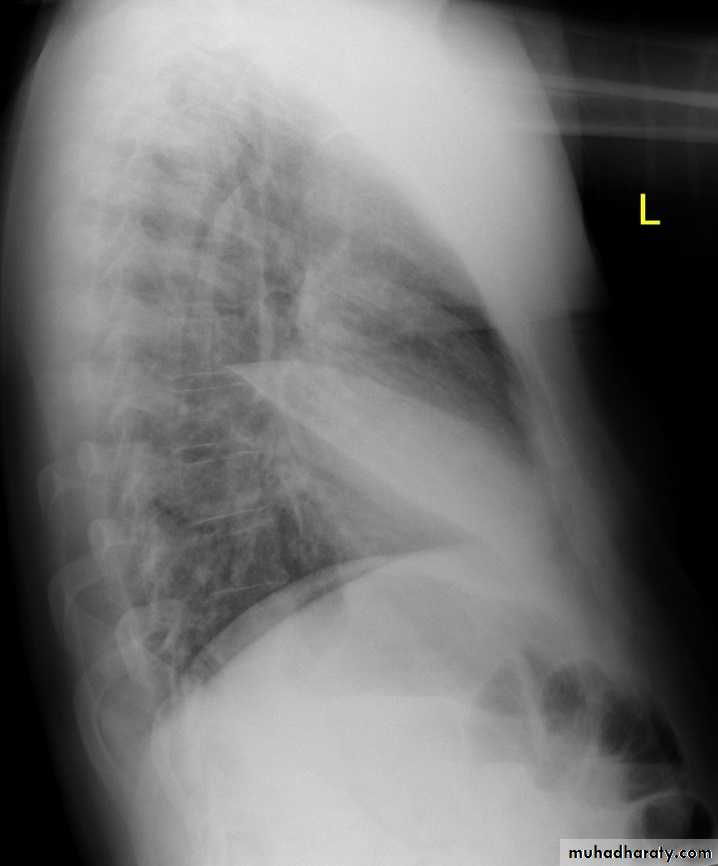

Right middle lobe collapse has distinctive features, and is usually relatively easily identified.

Radiographic features

Chest radiograph

Frontal chest XR showing opasity cause obscuration of the RT cardiac border

Lateral chest XR film the opacity is tongue like shape

versus (triangular in shape) in RT middle lobe consolidation seen in lateral chest XR film